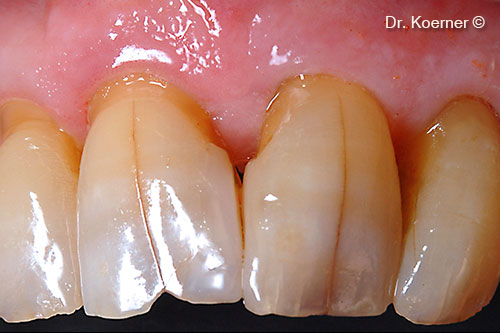

Clinical situation 4 months post-op with splinting

Removal of splinting before interproximal restauration